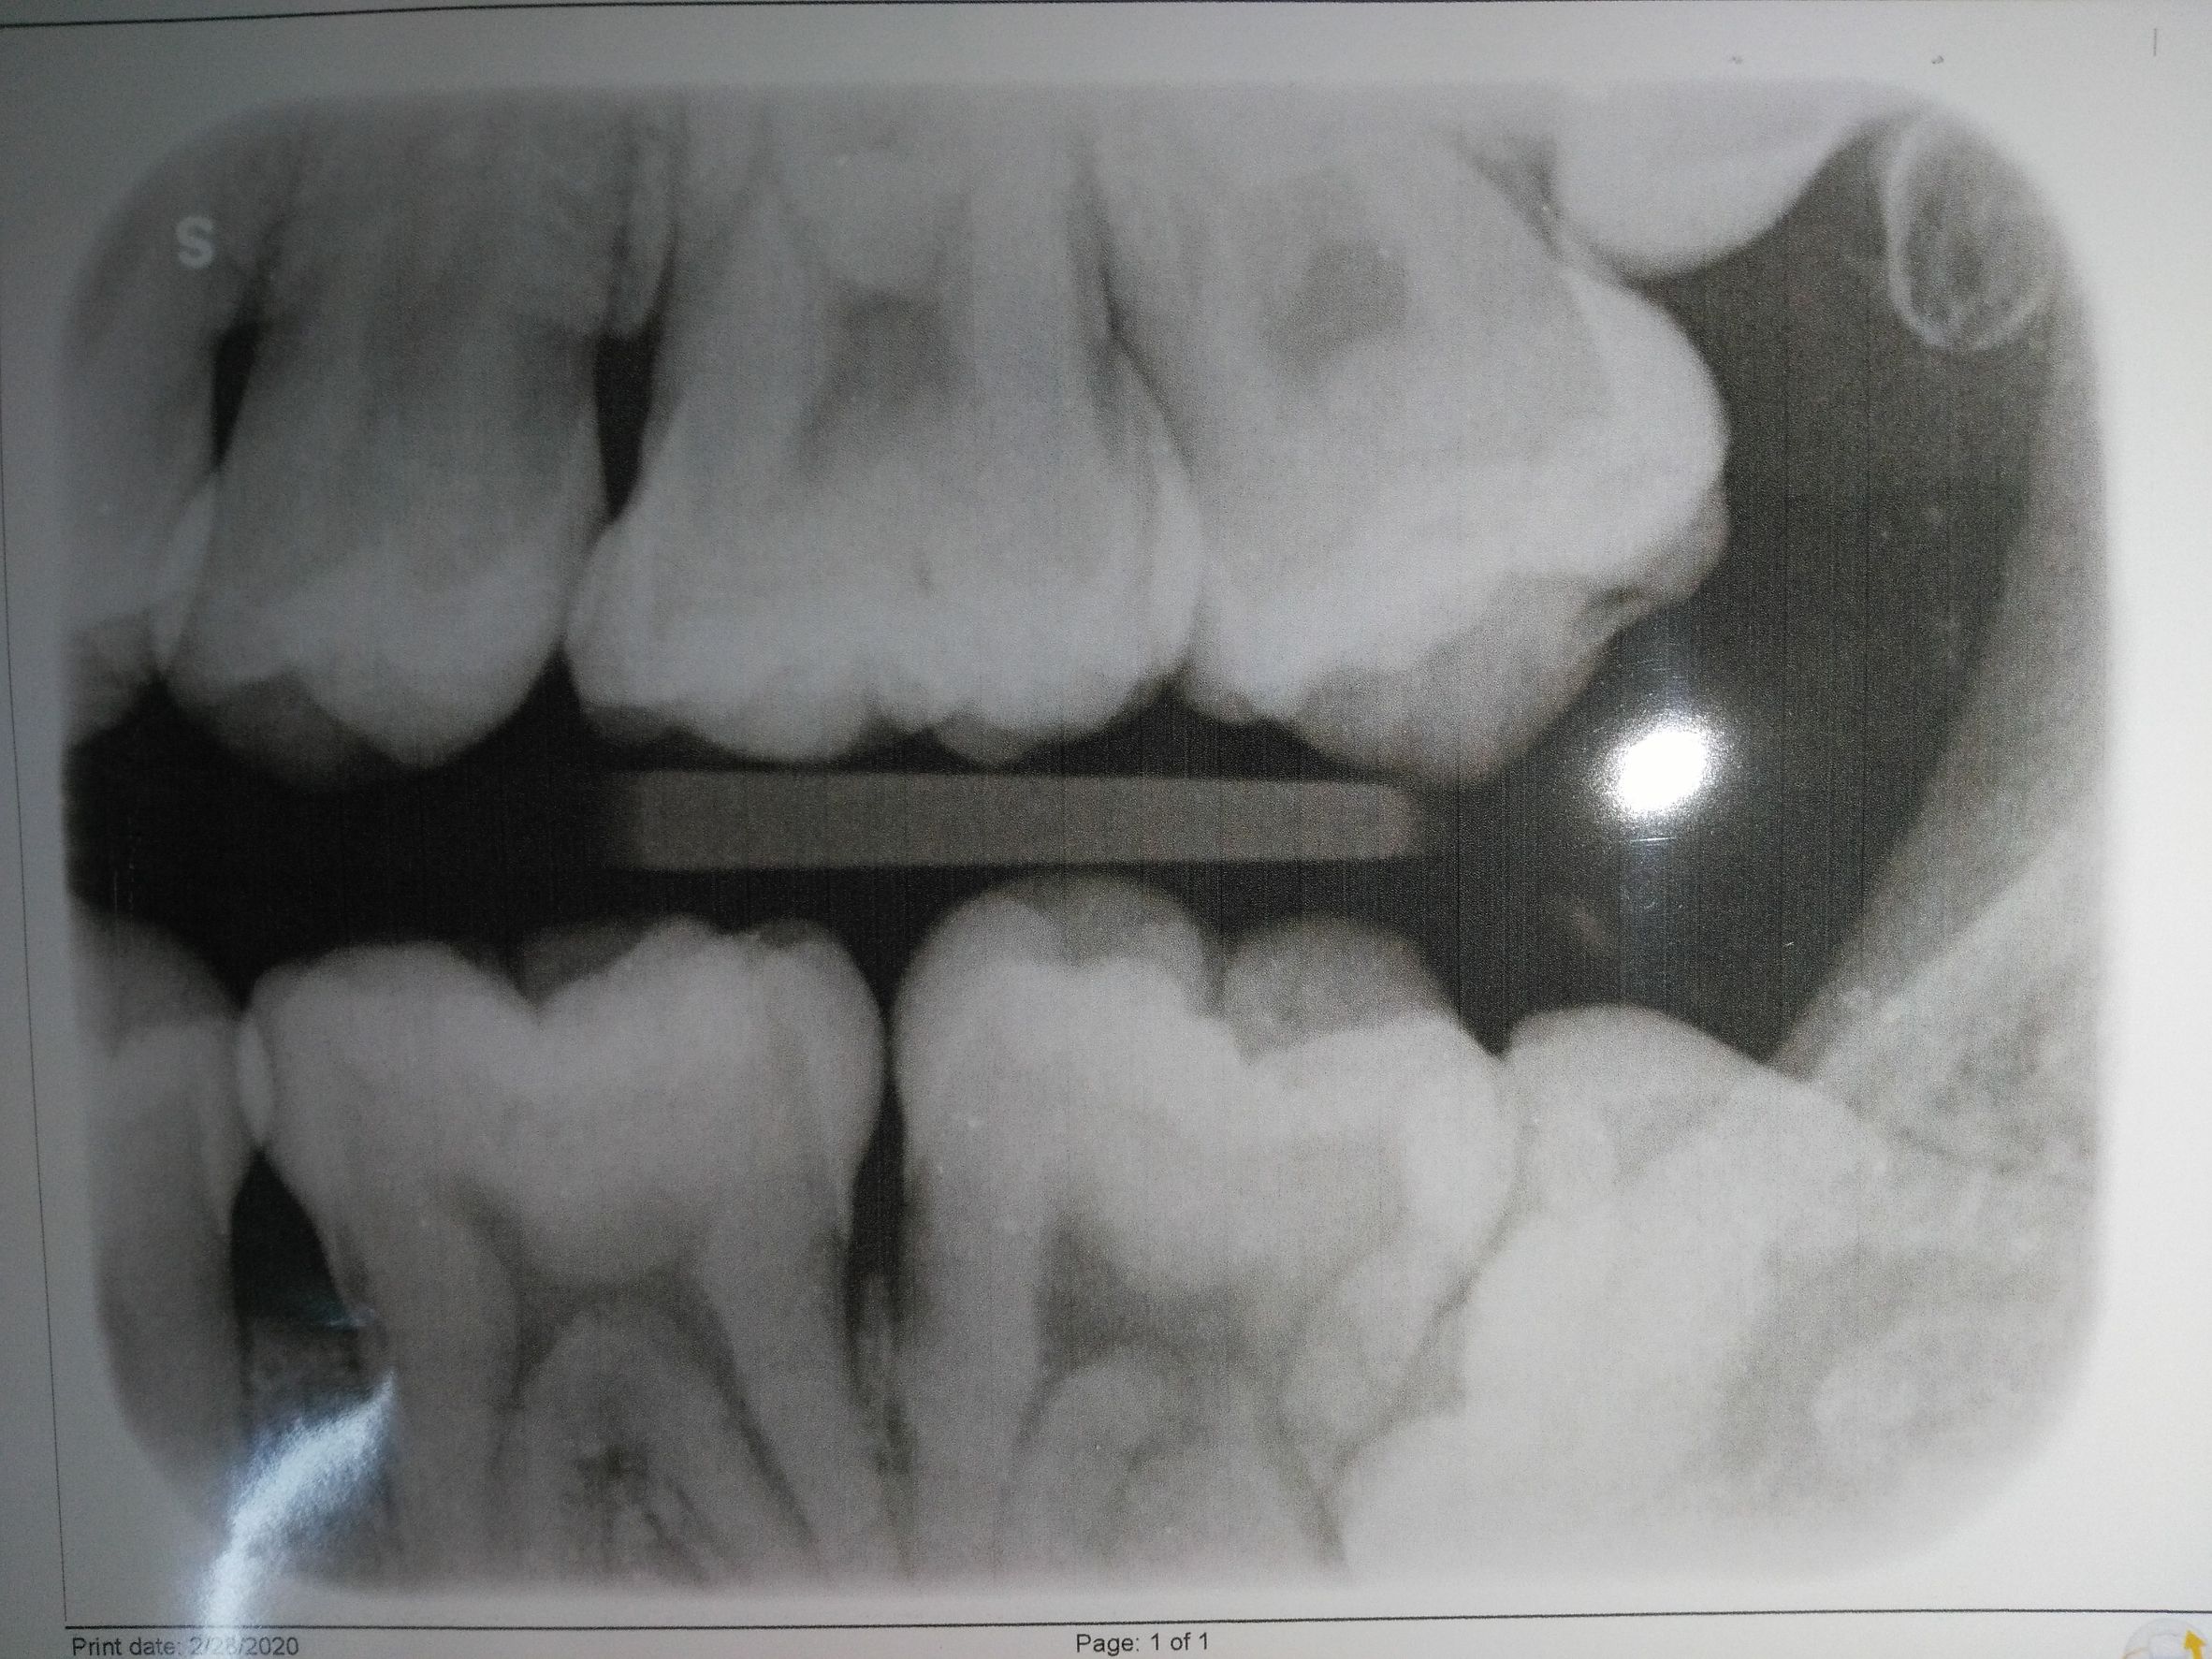

สอบถามหน่อยครับ ตอนนี้ผมมีฟันคุดอยู่ 2 ซี่ ซี่หนึ่งขึ้นเฉียงๆ อีกซี่นอนอยู่โผล่มานิดเดียว หมอแนะนำให้ผ่าออกทั้ง2 พอดีจะถึงคิวแล้ว เลยมาคิดว่าจะผ่าดีหรือยกเลิก เพราะที่ผ่านมาไม่เคยมีอาการอะไร ไม่ปวดไม่ผุไม่เสียว ใช้ชีวิตปกติ อยากได้ความเห็นทั้งคนที่ตัดสินใจผ่า หรือคนที่ปล่อยเอาไว้ รวมถึงถ้ามีทันตแพทย์มาอ่าน ช่วยตอบด้วยก็ได้ครับ (มีรูป)